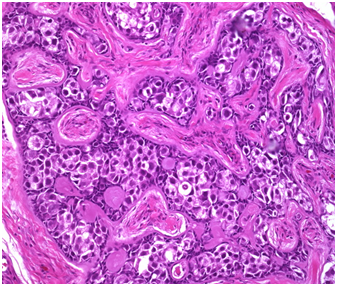

Informed consent was taken for Laparoscopic bilateral gonadectomy. At laparoscopy the uterus was not seen and right gonad was seen near deep inguinal ring (DIR) (Figure 1). Left gonad was not visualised near DIR (Figure 2). It was felt beyond superficial inguinal ring subcutaneously near pubic bone.DIR was closed with vicryl. A bilateral gonadectomy was done. Histopathology confirmed bilateral testicular tissue with sertoli cells only (Figure 3). She was advised a noevagina creation later.

Figure 3 Seminiferous tubules with sertoli cells only.